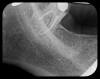

Some representative radiographic PSP images are exhibited here for demonstration of the anatomy and pathology that can be visualized with this technology. Many of these images would not have been possible if HW technology were used (Figure 3 through Figure 8).

As displayed here, the 2D radiographic images in Figure 3 through Figure 8 can alert the clinician to the need for a further 3D CBCT analysis to properly ascertain the anatomy and extent of the pathology that is initially visible in the intraoral radiographs. Proper treatment or referral to the appropriate specialty practice can follow.5,6 No. 2 PSP radiographs, when used in a conventional full-mouth series of radiographs on a patient with a relatively complete dentition, will routinely allow visualization of the anatomy of third molars, mandibular canal, maxillary sinuses, full dental root morphology, and bone anatomy beyond the apices2,16,17 (Figure 9 and Figure 10).

Fig 4. Severe dilaceration of root of tooth No. 17 and

curvature of roots of No. 18. Mandibular canal and inferior border of mandible are

easily visualized. If extraction of No. 17 is planned, a 3D CBCT study is required

due to proximity of tooth root to vascular and inferior alveolar nerve contents of

mandibular canal and possibility of surgical complications.

Figure 4